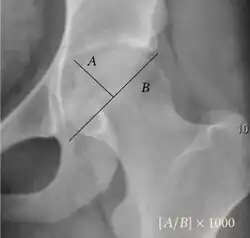

- Reimer's migration index (MI), also called the femoral extrusion index,[3] is calculated if hip dysplasia is detected. It can be used to indicate hip dislocation. It is the horizontal distance (parallel to the Hilgenreiner Line) between the Perkin line and the lateral border of the ossification center of the femoral head, divided by the horizontal width of the ossification center. The migration index is normally less than 33% by most sources,[9] but 25% and 30% has also been suggested.[10]

| Reimer's migration index[9] |

|

The percentage of the femoral head that lies outside of the acetabular roof. It is also called the femoral extrusion index. | <25% |